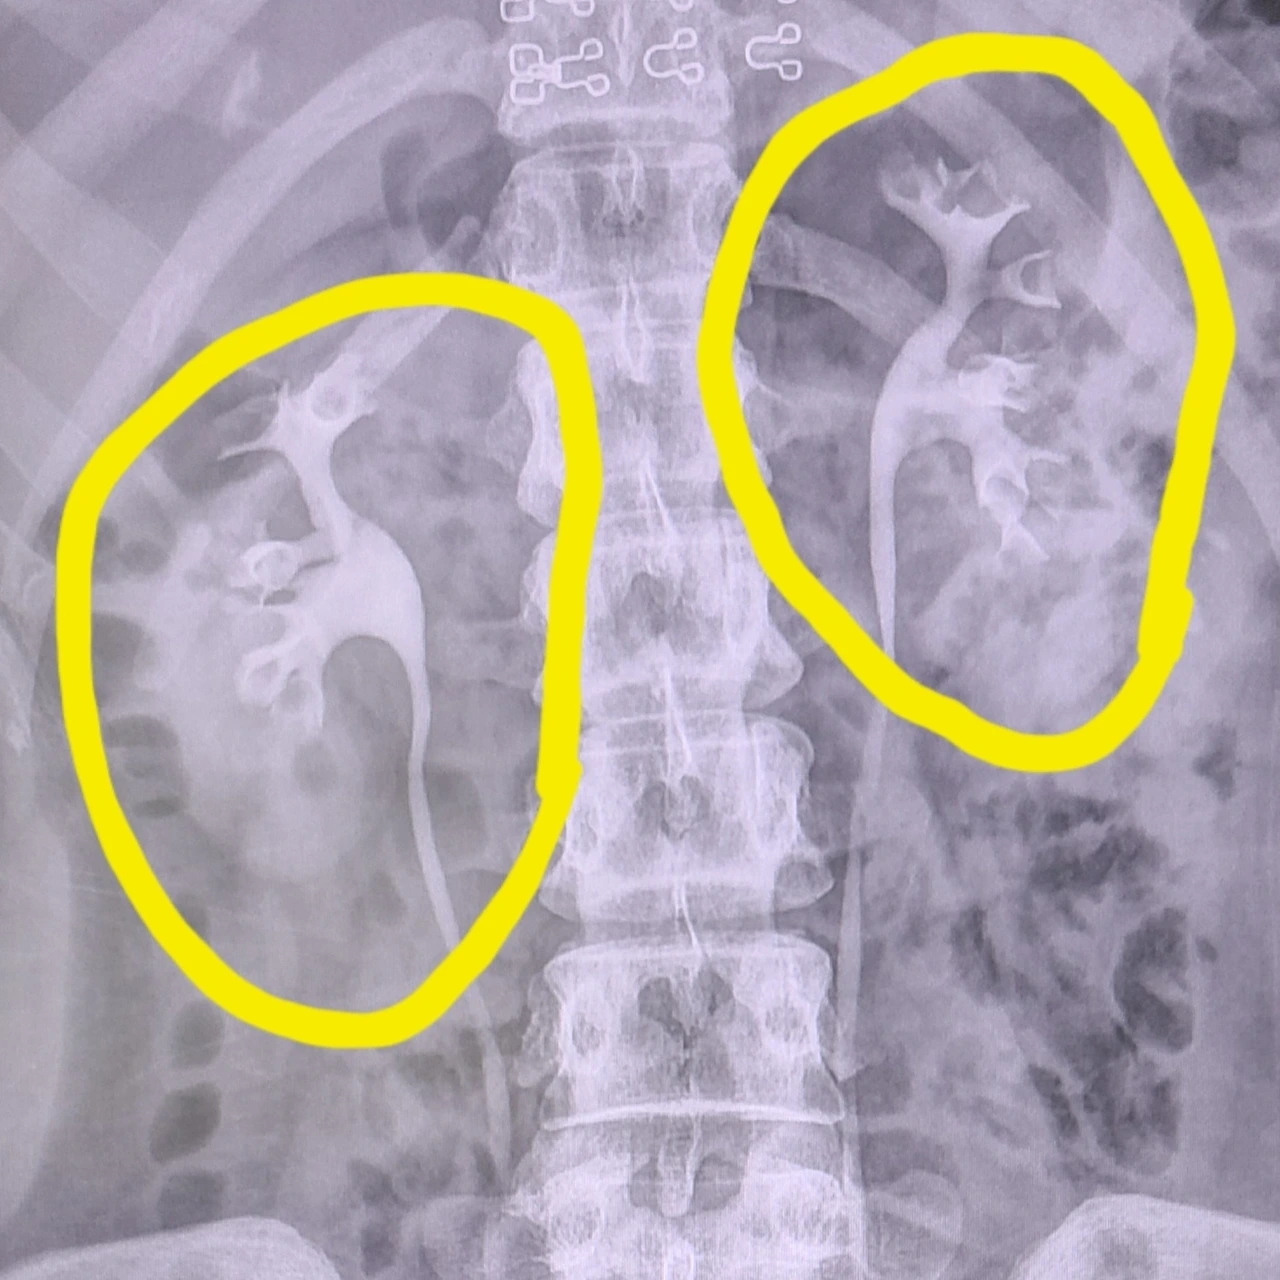

얼마 전부터 몸이 붓고 화장실도 못 가고 조금만 일해도 힘들어서 병원에 갔더니 오른쪽 콩팥이 심하게 부어있고 돌로 혈관이 막혀 있는데 계속 놔둘 경우 콩팥 기능을 잃을 수도 있다는 진단을 받았다.

치료로 쇄석술을 결국 받았는데 이게 뭐냐 의사선생님께 물으니 음파로 해당 부위에 40분동안 체외충격파를 쏴서 돌을 쪼개는 거라고 하시더라. 선생님이 조금 따끔거리는 정도라 했지만 시작부터 진통제 링거 맞는 것부터 합리적인 의심이 들기 시작, 시술이 끝난 후부터 본격적인 고통이 시작됐다. (참고할 자세한 설명은 네이버에 '체외충격파쇄석술 후기' 검색 요망.)